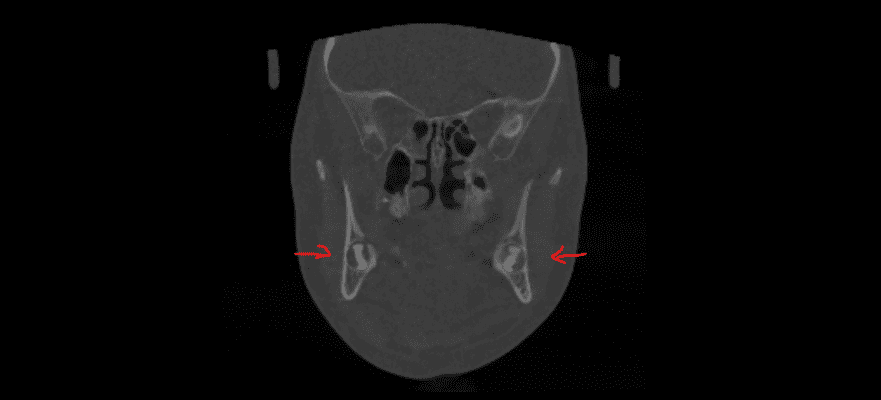

Дівчинка 4,5 років скаржилась на біль в нижньому зубі справа. В зв’язку з високою складністю процедур і значним об’ємом лікування (8 зубів) та після невдалої спроби лікування в звичайному режимі було прийнято рішення про лікування в умовах анестезіологічного забезпечення. Видаленно запалену пульпу (“нерв”) та проведено лікування каналів нижнього зуба ліворуч, цей та сусідні зуби покриті металевими коронками через значний об’єм ураження. Проліковані всі зуби, які потребували допомоги, щоб в майбутньому уникнути болю, дискомфорту та поширення інфекції. Через три години лікування дівчинка може комфортно жувати і не відчувати болю і дискомфорту.